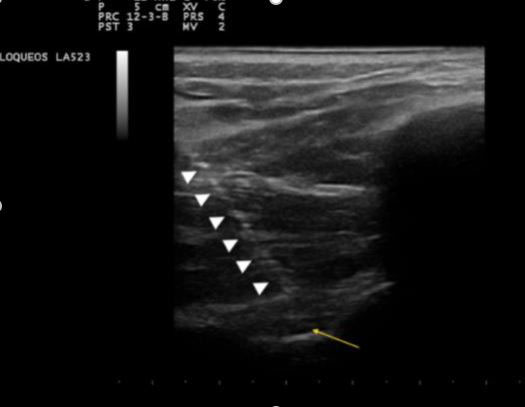

Ekografia bidez identifikatzen da nerbioa non dagoen, eta, horretarako, zunda ekografiko lineala (7-13 MHz) erabiltzen da; zunda hau plano koronalean jartzen da hodi supraeskapularraren gainean, nahiz eta batzuetan zunda convex bat ere (2-5 MHz) erabiltzen den gorputz handiagoa duten pazienteetan.